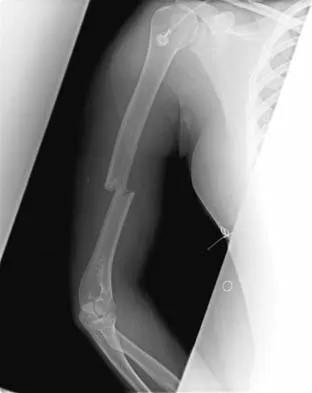

A 20-year-old woman sustained the closed injury shown in Figures 49a and 49b in a motor vehicle accident. Examination reveals that this is an isolated injury; however, she has a complete radial nerve palsy. Management should consist of

Explanation

Lacerated radial nerves are associated with open humeral fractures. All open humeral fractures with radial nerve palsy should be managed with radial nerve exploration and skeletal stabilization. Closed humeral fractures with associated radial nerve palsy usually have an intact nerve with neurapraxia. Most of these patients recover without surgical treatment. If the patient has multiple injuries, skeletal stabilization may be indicated to improve mobilization. For an isolated closed humeral fracture with a radial nerve palsy, the treatment of choice is splinting for 1 to 2 weeks, followed by a humeral fracture brace. Ring D, Chin K, Jupiter JB: Radial nerve palsy associated with high-energy humeral shaft fractures. J Hand Surg Am 2004;29:144-147.